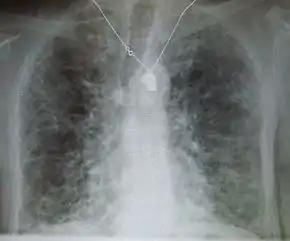

X-rays

Chest radiography is usually the first test to detect interstitial lung diseases, but the chest radiograph can be normal in up to 10% of patients, especially early in the disease process.[12][13]

High resolution CT of the chest is the preferred modality, and differs from routine CT of the chest. Conventional (regular) CT chest examines 7–10 mm slices obtained at 10 mm intervals; high resolution CT examines 1–1.5 mm slices at 10 mm intervals using a high spatial frequency reconstruction algorithm. The HRCT therefore provides approximately 10 times more resolution than the conventional CT chest, allowing the HRCT to elicit details that cannot otherwise be visualized.[12][14]

Radiologic appearance alone however is not adequate and should be interpreted in the clinical context, keeping in mind the temporal profile of the disease process.[12]

Interstitial lung diseases can be classified according to radiologic patterns.[12]